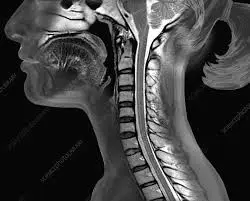

이 글은 경추 MRI 결과지를 받아든 환자 입장에서

반드시 짚고 넘어가야 할 포인트를 정리한 글입니다.

2. 환자가 반드시 확인해야 할 첫 번째 포인트 : 위치

경추 MRI 결과지에는 보통 이런 표현이 나옵니다.

- C4-5

- C5-6

- C6-7

이 숫자는 목뼈 번호 + 신경이 나오는 위치를 의미합니다.

왜 이게 중요할까요?

- 손 저림이 어느 손인지

- 어느 손가락이 불편한지

- 팔 어느 쪽이 약한지

이 증상들과 위치가 연결되기 때문입니다.

즉, 증상과 MRI 위치가 맞아떨어지는지가 첫 번째 확인 포인트입니다.